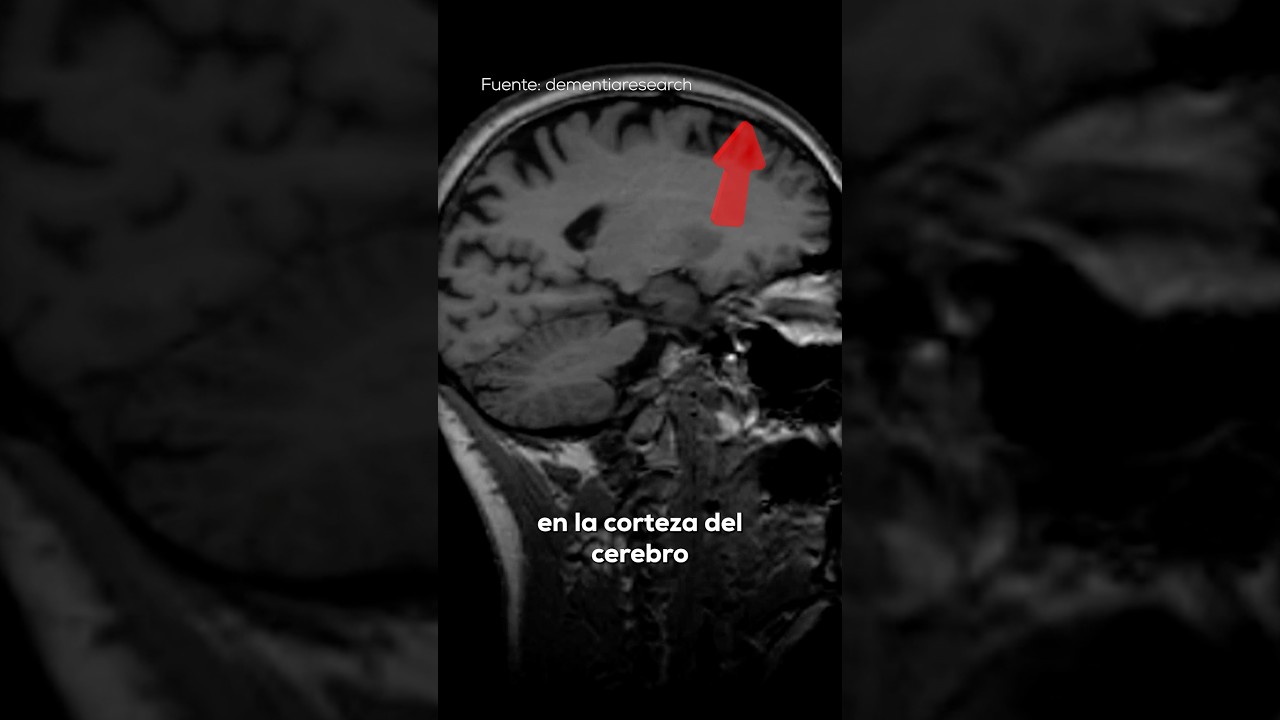

- Atrofia cortical: Afecta principalmente la corteza cerebral, la capa externa del cerebro que está involucrada en funciones como la memoria, el pensamiento y la percepción sensorial.

- Resonancia magnética (RM): Utilizada para observar cambios en la estructura cerebral.